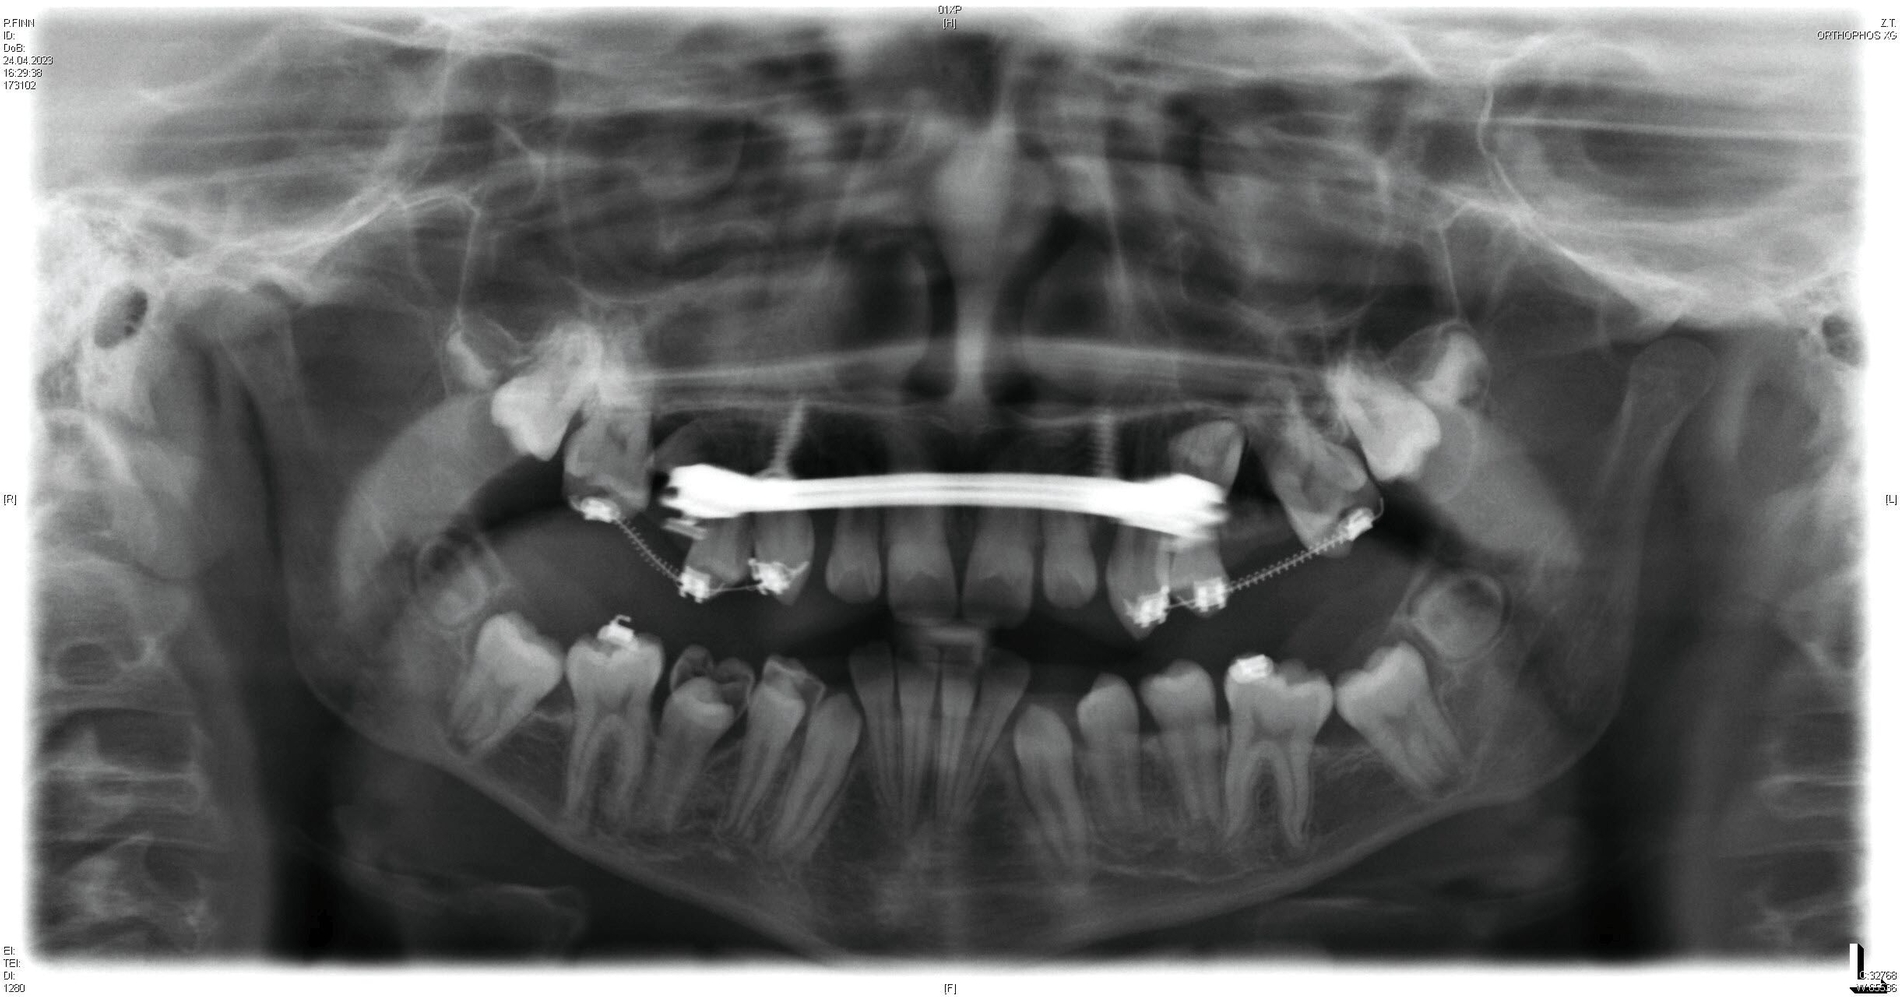

Das Endergebnis ist in der Panoramaschichtaufnahme in Abbildung 6 gezeigt, in der beide Mini-Implantate keine Anzeichen einer periimplantären Osteolyse aufweisen. Während des Behandlungszeitraums von insgesamt 31 Monaten wurden keine unerwünschten Nebenwirkungen beobachtet.

Ein zwölfjähriger Patient stellte sich in der Poliklinik für Kieferorthopädie des Universitätsklinikums Tübingen mit einer skelettalen Klasse-III-Konfiguration, einer Angle-Klasse III, einem Kreuzbiss auf der linken Seite und transversal schmalem Oberkiefer vor. Die Anamnese ergab ein vermindertes Hörvermögen, weshalb der Patient Hörgeräte trug. Darüber hinaus wurde keine Medikamenteneinnahme oder Allergie angegeben. Er wies mit einem dentalen Alter von sieben Jahren einen verzögerten Zahndurchbruch auf. Der initiale intraorale Befund zeigte die in situ befindlichen Zähne 11, 21 und 32–42. Die Zähne 12 und 22 eruptierten in Inklinationsfehlstellung. Die Milcheckzähne und -molaren befanden sich noch in situ. Die Sechsjahrmolaren waren nicht eruptiert und zeigten eine Verlagerungstendenz, insbesondere im Unterkiefer (Abbildung 1, Tabelle 1).

Die initiale Panoramaschichtaufnahme zeigte die Verlagerung mehrerer Zahnkeime sowie einen Platzmangel der Eckzähne und der Prämolaren im Oberkiefer (Abbildung 1b). Die Keimkrone von Zahn 13 wies dabei eine enge Lagebeziehung zum Zahnkeim 12 auf (Abbildung 1b). Die bereits eruptierten permanenten Frontzähne zeigten eine Angulations- und eine Inklinationsfehlstellung. Im distalen Bereich waren keine Durchbruchshindernisse erkennbar. Vor Beginn der kieferorthopädischen Behandlung wurde eine Primäre Zahndurchbruchsstörung (Primary Failure of Eruption – PFE) genetisch ausgeschlossen.